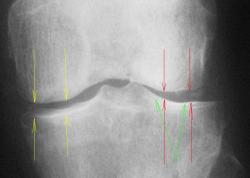

1. По всей видимости, необходимо иметь в виду феморо-пателлярный артроз. Конечно, мы не можем оценить ширину суставной щели в феморо-пателлярном суставе, так как боковой снимок сделан не в строгой боковой проекции и суставная щель, как таковая, не дифференцируется. Но можно заподозрить наличие субхондрального склероза - помечен красными стрелками и мелкие субхондральные кистовидные (точечные) просветления - желтые стрелки.

2.Оценивая ширину суставной щели необходимо отметить её неравномерность по ширине - некоторое расширение в латеральных отделах-красные стрелки, по сравнению с медиальными отделами желтые стрелки. Почему расширение латерально, а не сужение медиально? Медиально конгруентность суставных поверхностей сохранена, латерально - конгруентность нарушена - некоторая клиновидность. В области латерального мыщелка б/берцовой кости "намечается" субхондральный склероз - зеленые стрелки.

На фоне суставной щели латерально определяются локальные уплотнения - красные стрелки - локальные обызвествления сумочно-связочных компонентов сустава (по С.А. Рейнбергу), но по всей видимости, это локальные отложения солей Са в "травмированном" мениске, что может свидетельствовать о функцинальной несостоятельности последнего. Точечное уплотнение дифференцируется и медиально - синяя стрелка.

3.Оценивая межмыщелковые возвышения, можно констатировать, что латеральное межмыщелковое возвышение, "кажется несколько больше" (по сравнению с медиальным). Определяется "заострение" и "деформация" вершины латерального межмыщелкового возвышения за счет локального окостенения связки - сиреневая стрелка, что косвенным образом свидетельствует о функциональной несостоятельности этой связки.